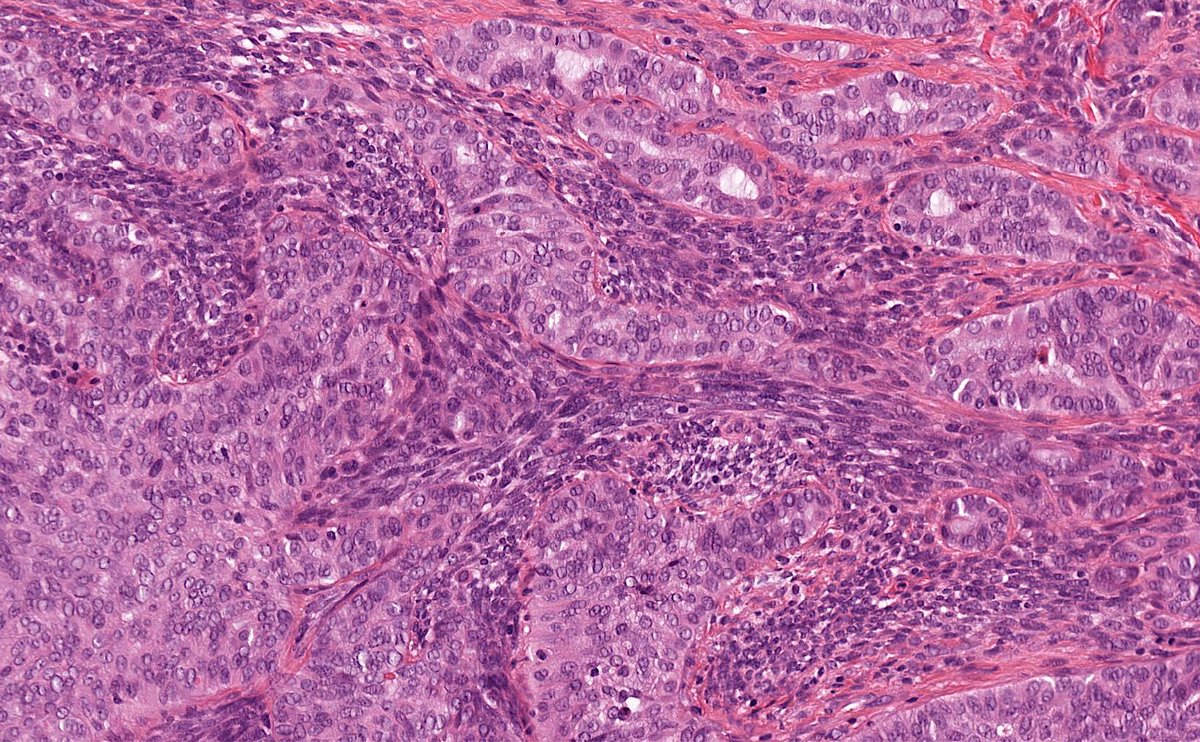

70M with parotid mass. What is your diagnosis?